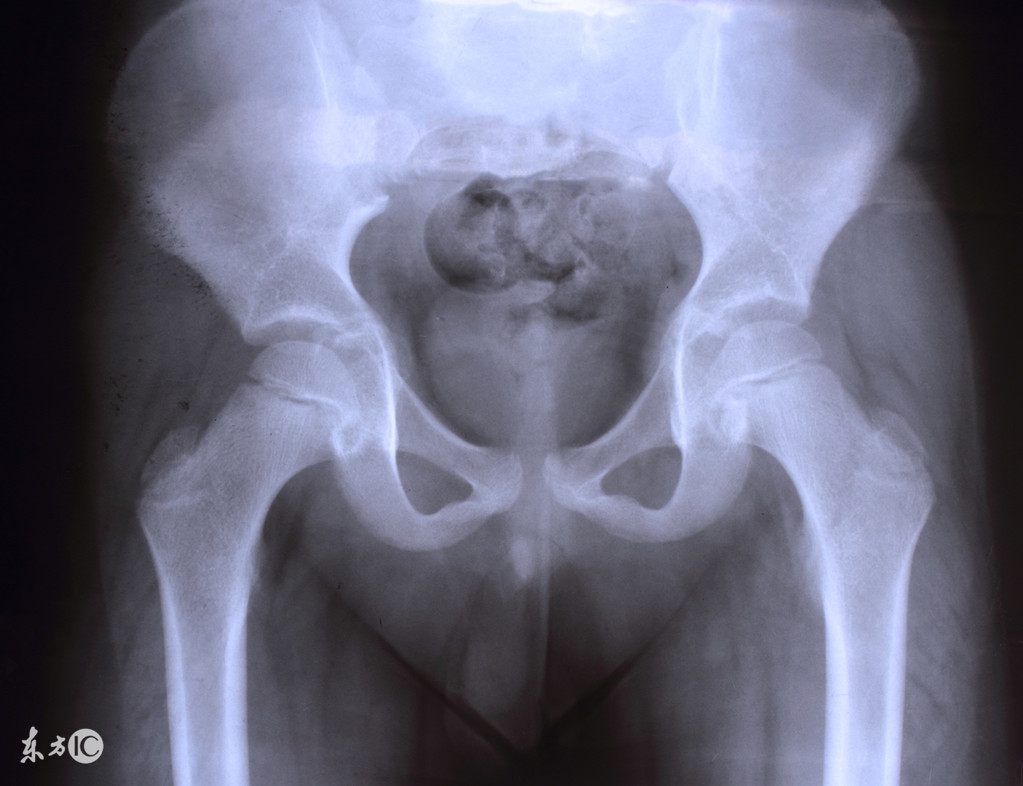

盆腔积液是盆腔存在炎性渗出物,可发生在子宫内膜发炎后,内膜组织肿胀的细胞中渗出的略黏稠的液体,被周围组织包裹所渐渐形成的囊性包块。“盆腔积液是一种表现而不是一种疾病,有很多疾病的发生都会表现为盆腔积液。”吴素慧说。

女性腹膜腔内有肠管、大网膜、子宫、输卵管、卵巢、肝脏等脏器,这些脏器位于腹膜内位器官。腹膜覆盖腹腔脏器及盆腔与腹腔表面,腹膜可漏出少量液体,称为腹膜漏出液。这样的漏出液多为淡黄色,稀薄透明,可避免腹膜腔内的脏器相互粘连,对肠道蠕动起润滑作用。正常情况下,腹腔漏出液一般少于200ml,盆腔是腹膜腔的一部分,站立时处于低位,卧位时子宫、直肠凹处于腹膜腔的最低位。因此,超声检查时可见子宫直肠凹内有液性暗区,也称为盆腔积液。

“妇科门诊多见的盆腔积液,实际上为正常生理现象,不必惶恐。”吴素慧告诉记者,盆腔积液可分为生理性盆腔积液和病理性盆腔积液两种。女性在排卵时,由于卵泡液的排出及排卵创口的渗血,这时积液量可有所增加。有时甚至可在超声检查时见到排卵,此时盆腔积液量也会有所增加。这种腹膜漏出液以及排卵产生的卵泡液等,均可导致盆腔积液,这种积液属于正常的生理现象,不需要治疗。